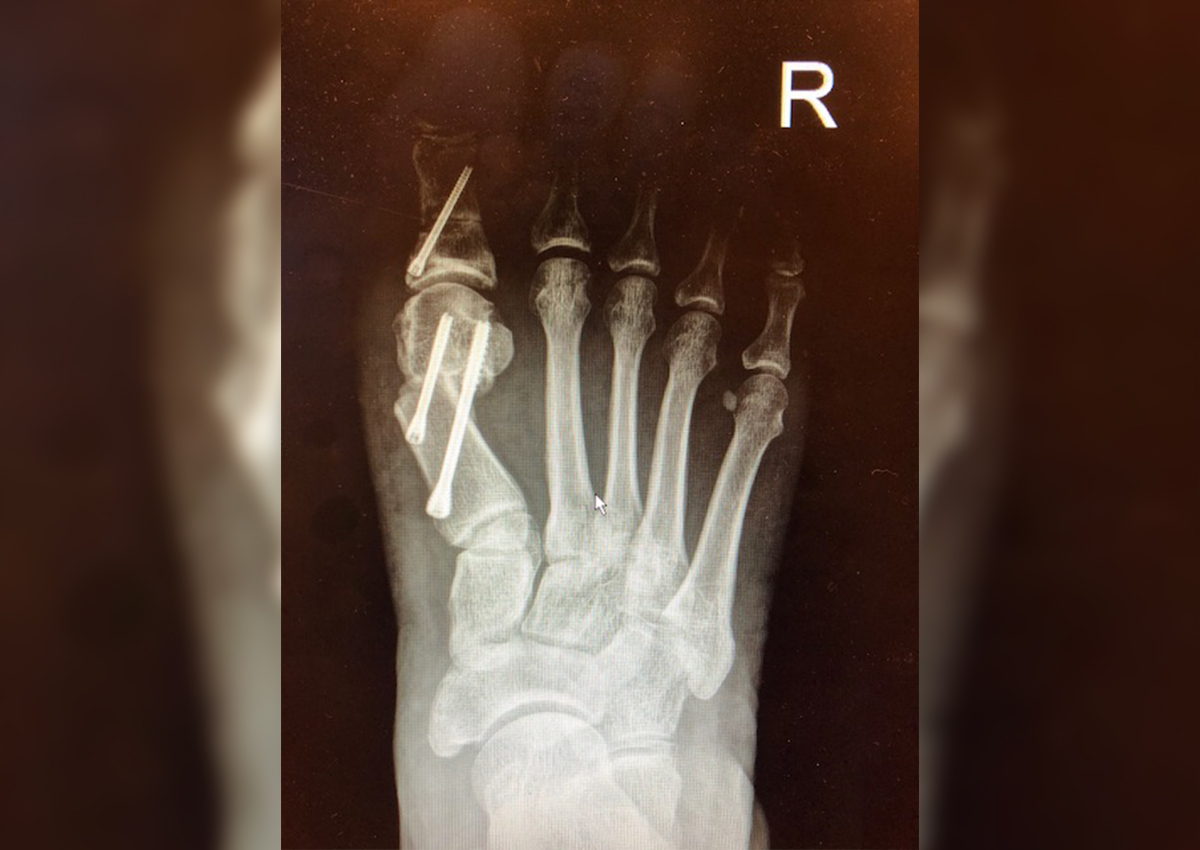

But now, with a new minimally-invasive surgery, patients can have the deformity fixed at an early stage with just a few keyhole insertions.

While it may be slightly more expensive, depending on the severity of the bunion, every surgery requires a new set of burrs (surgical drill) and the entire process is X-ray guided.